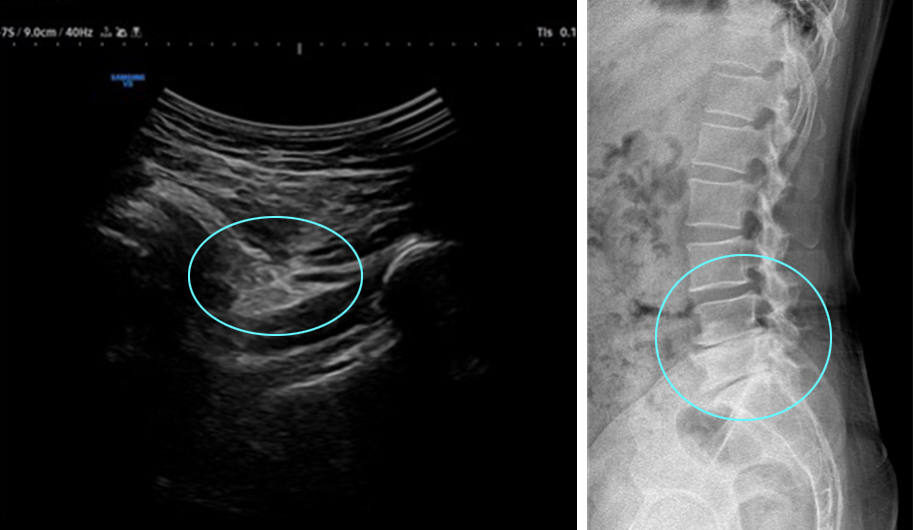

허리 협착 및 디스크 수술 후 허벅지 뒤쪽 및 내측으로 통증 지속되던 50대 환자.

좌골 신경에 하이펑쳐 주사 치료로 호전됨

하이펑쳐 주사

조직재생 유도 물질로 잘 알려진 PDRN과

자하거(태반)를 환자별 맞춤 배합하여 초음파를 보며

고관절·허벅지 통증 병변에 주입